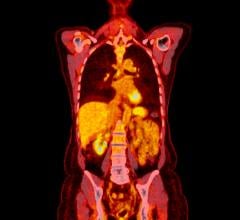

Image courtesy Siemens Healthcare

The good news for molecular imaging is that the latest generation of PET/CT can visualize more and subtler signs of disease. Even better, these souped-up machines can more precisely measure standard uptake values (SUVs). This adds credence to their role in quantifying what has long been a subjective process of diagnosing, prognosing and following patients.